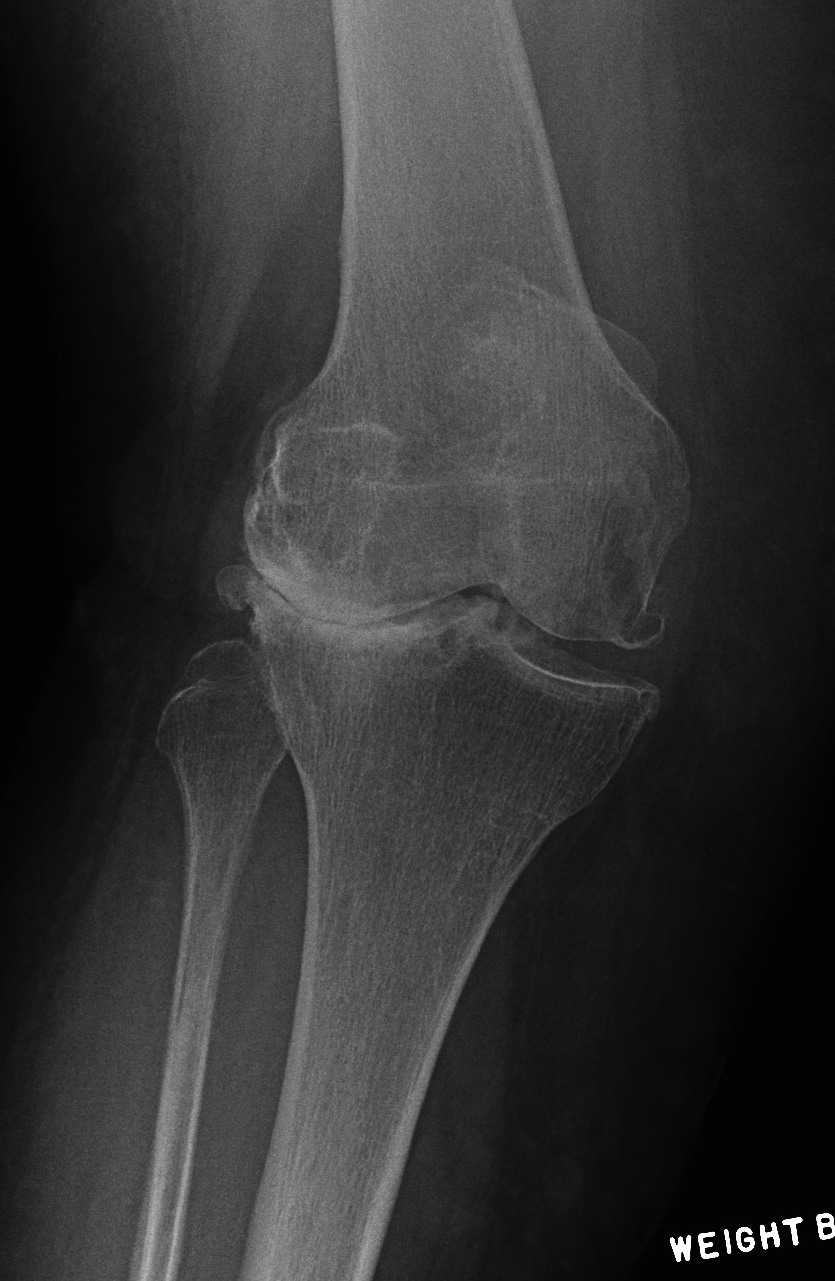

Tibial resection

- don't take 10 mm as bone worn laterally in valgus OA

- can't take 2mm off medial side as is the normal side

- need to estimate

- take 6 mm from lateral tibia intially, stay above fibula head

- much more symmetric proximal tibial resection

- use trial blocks to assess flexion / extension gaps

TKR Valgus OA Tibial Resection

Deficient lateral tibial plateau

- don't take > 10 mm medial plateau

- will get down into soft bone

- preop plan

- may need augments laterally and therefore stems

- below xray is borderline / but just ok

TKR Severe Valgus Tibial Resection Planning